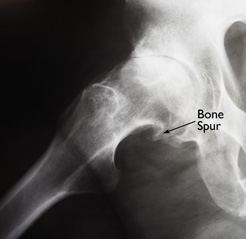

Common Causes of Hip Pain

A hip with osteoarthritis.

This x-ray shows a large bone spur that has developed on the ball of an arthritic hip.